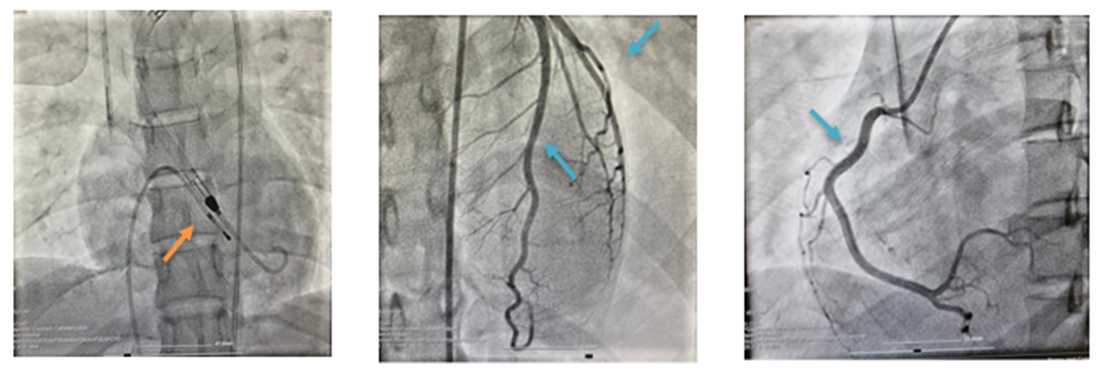

Despite ECG findings suggestive of LAD-territory STEMI, the cardiology team deferred immediate coronary angiography and instead pursued maximal medical therapy followed by mechanical support. They opted for this approach due to the patient's young age and absence of underlying cardiac disease [7]. Moreover, the inconsistency between the ECG rhythm, biomarker pattern, and the TTE findings (diffuse dysfunction with preserved apical and anterior function) strongly suggested infective myocarditis over the initial diagnosis of STEMI. Therefore, the deferral for urgent coronary angiography was justified. However, it was pursued at a later stage to definitively exclude any findings suggestive of ischemia at the level of the coronary arteries. By 24 hours post-admission, the patient was still in a state of refractory shock. At this point in the patient’s management, mechanical support became essential. As the patient was deemed high-risk, angiography was coupled with Impella implantation (Figure 2A) to minimize complications. As anticipated, angiography revealed patent coronary arteries (Figures 2B and 2C).

Figure 2A: Impella in position Figure 2B: LAD and LCx view Figure 2C: RCA view

Orange arrow: Impella device inserted Blue arrow: patent coronary arteries

The Impella device was inserted via femoral artery access and provided support for five days. Repeat echocardiography demonstrated progressive recovery of ventricular function from 20–25% at presentation to 60–65% on day 5. Additionally, the ECG on day five showed resolution of ST-elevation and LBBB morphology with return to normal sinus rhythm. Hemodynamic stability was achieved with no further need for inotropic or vasopressor agents. Her stable condition justified Impella removal on day five, which was complicated by the development of right femoral artery dissection and subsequent limb ischemia. Immediate vascular surgery was scheduled to restore perfusion, with a successful final outcome.